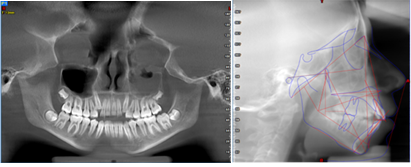

Al analizar las fotografías intraorales revelaron lo siguiente (Figura 2): Fotografía frontal: líneas medias dentales no coincidentes la inferior se encuentra con una desviación de 2 mm hacia la derecha, mordida abierta y caninos superiores ectópicos. (A). Fotografía lateral derecha (B) e izquierda (C): Clase II molar, clase canina no aplica debido a que los caninos no se encuentran en el arco.

Fotografía oclusal superior: Forma de arcada ovoide, apiñamiento en el sector anterior, palatinización de las piezas 1.2 y 2.2, piezas 1.3 y 2.3 ectópicas, paladar profundo (D). Fotografía oclusal inferior: Forma de arcada oval, lingualización de las piezas 4.5 y 4.6, ausencia de la pieza 3.7 (E). Fotografía de resalte: La sobremordida horizontal y vertical de -2 mm (F).

Figura 2. Evaluación inicial intraoral y radiográfica

Elaboración: Los autores.

El análisis de discrepancia se realizó sobre los modelos de estudio obteniendo una discrepancia superior de - 4mm y una discrepancia inferior de -1.8 mm (G). En la ortopantomografía se observa que el seno maxilar izquierdo aparece velado, presencia de los 4 gérmenes de los terceros molares, cornetes hipertróficos, no se visualiza ensanchamiento del ligamento periodontal, no existen patologías periapicales (H). Los estudios cefalométricos que se realizaron fueron Rickkets, Jaraback y Steiner, obteniendo como resumen: patrón esqueletal Clase II por protrusión maxilar, a nivel de incisivos: protrusión y proinclinación del incisivo superior e inferior, VERT: +0,69 dándonos un patrón facial: braquifacial suave, en las esferas rotacionales de Jarabak: 54% indicándonos una tendencia a crecimiento rotacional posterior (I).